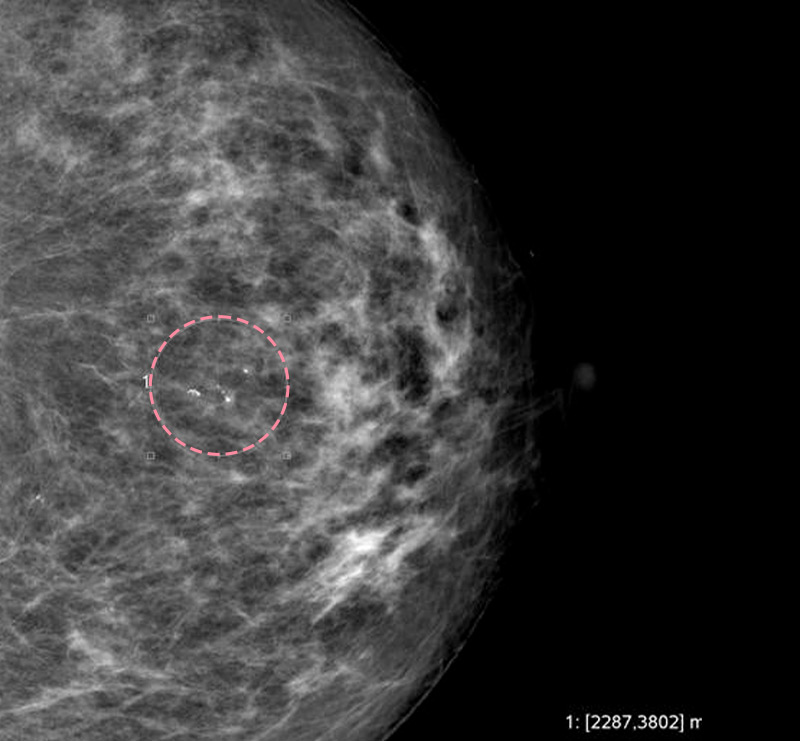

매우 빠르게 자라는 유방 종양 수술을 위해 외국에서 내원한 17세 환자의 사례입니다.

3cm 이상의 유방 종양은 외과적 수술로 제거하는 것이 원칙이고, 대부분의 경우 대학병원으로 연계됩니다.

그러나 한송이 원장은 대학병원에서의 고난도 시술 경력을 다수 보유하고 있어 크기가 큰 종양도 맘모톰 시술로 가능하였습니다.

3번에 걸쳐 맘모톰시술을 시행한 결과 성공적으로 제거를 마칠 수 있었습니다. 외과적 절제로 생길 수 있었을 흉터를 원치 않으셨던 환자와 보호자분 모두 시술 결과에 만족하셨습니다. 매년 추적 검사를 시행하고 있으며, 깨끗이 제거된 상태를 잘 유지하는 중입니다.